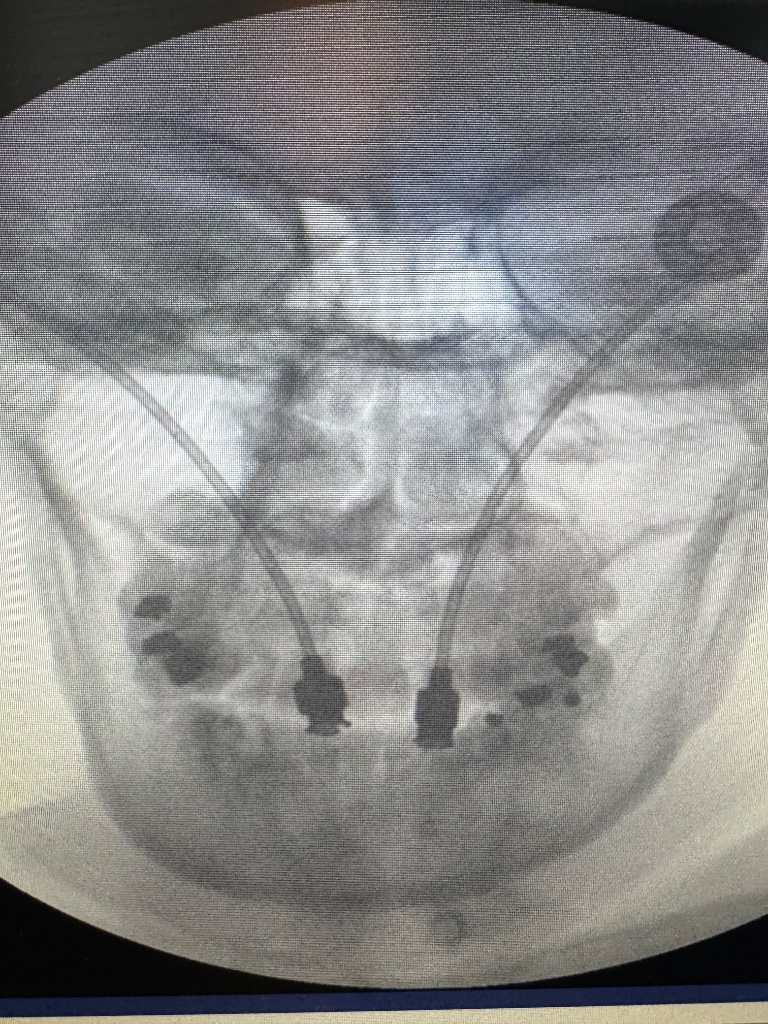

I have been migrating to the C2 DRG PNS approach for posterior scalp neuralgias. Satisfied patients. Less mechanical wear/tear as you aren't crossing the C0/C1/C2 movement axis and much lower risk of erosion with the depth in the scalp. External pulse generator on the chest or shoulder depending on patient preference

FYI, I found the pictures in the paper from Stanford quite interesting.

Can you link the paper? Where is the tip even? Is that in the canal? No complications?

I did one of these recently after the patient had tried, ESIs, C2-4 CRFA, GONB, PT, neck brace, meds, etc. Similar placement to the article with a shallower entry and dipped down to final target. Pt isn't a surgical candidate, older gentlemen, with kyphosis. He did excellent, during the trial, just implated, post op upcoming. I'll keep you posted.